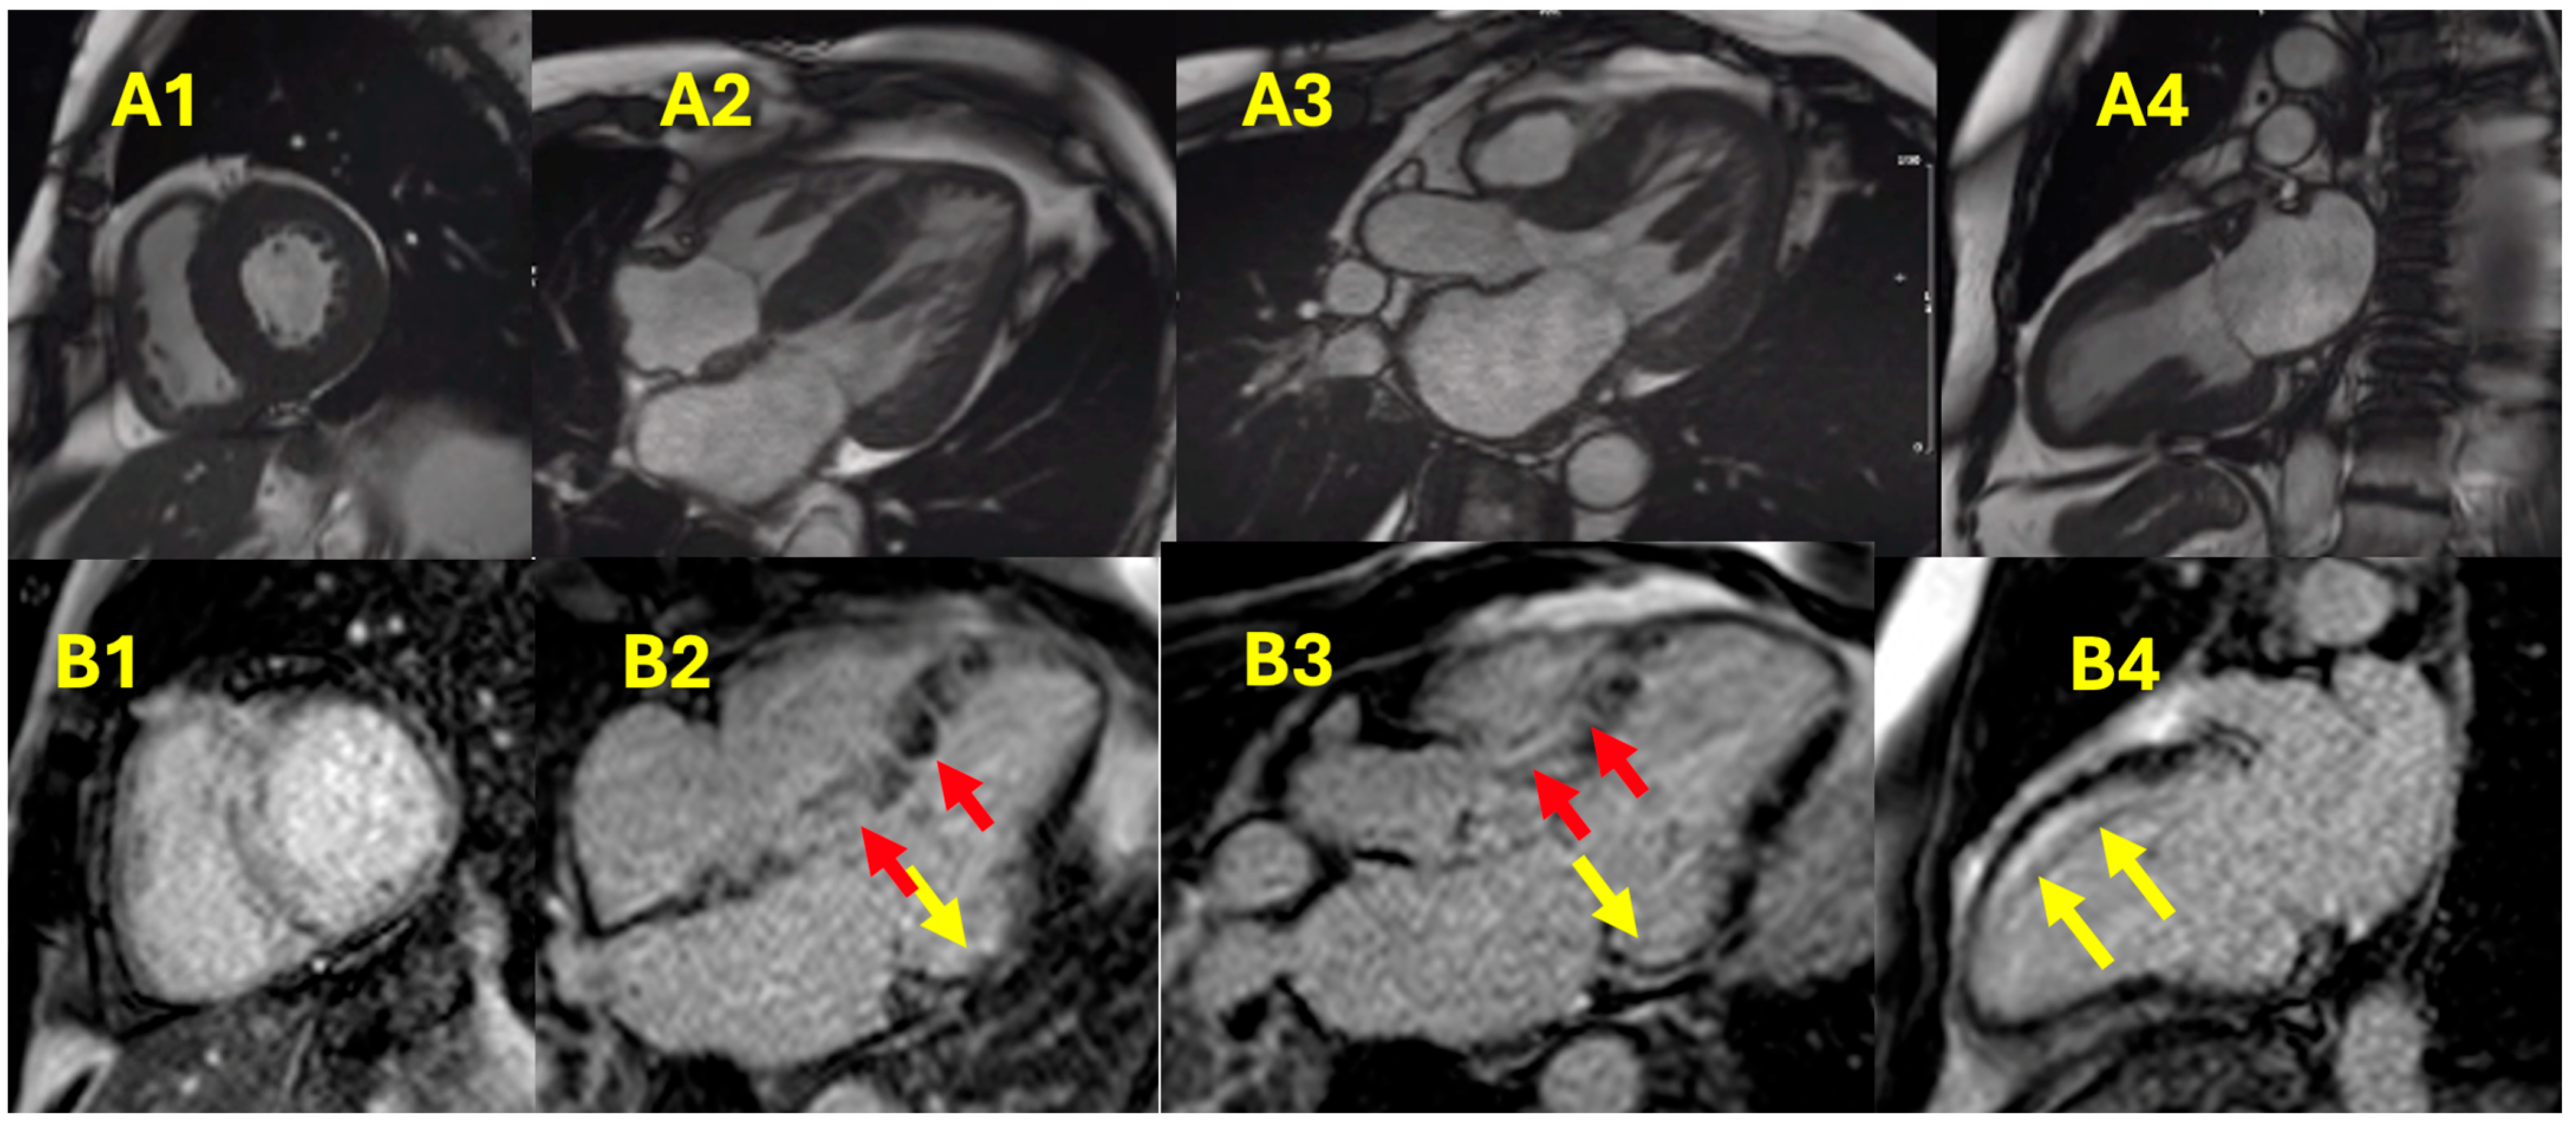

- Martinez-Naharro, A.; Treibel, T.A.; Abdel-Gadir, A.; Bulluck, H.; Zumbo, G.; Knight, D.S.; Kotecha, T.; Francis, R.; Hutt, D.F.; Rezk, T.; et al. Magnetic Resonance in Transthyretin Cardiac Amyloidosis. J. Am. Coll. Cardiol. 2017, 70, 466–477. [Google Scholar] [CrossRef] [PubMed]

- de Carvalho, F.P.; Erthal, F.; Azevedo, C.F. The Role of Cardiac MR Imaging in the Assessment of Patients with Cardiac Amyloidosis. Magn. Reson. Imaging Clin. N.Am. 2019, 27, 453–463. [Google Scholar] [CrossRef]

- Fontana, M.; Martinez-Naharro, A.; Hawkins, P.N. Staging Cardiac Amyloidosis With CMR: Understanding the Different Phenotypes. JACC Cardiovasc. Imaging 2016, 9, 1278–1279. [Google Scholar] [CrossRef]

- Fontana, M.; Pica, S.; Reant, P.; Abdel-Gadir, A.; Treibel, T.A.; Banypersad, S.M.; Maestrini, V.; Barcella, W.; Rosmini, S.; Bulluck, H.; et al. Prognostic Value of Late Gadolinium Enhancement Cardiovascular Magnetic Resonance in Cardiac Amyloidosis. Circulation 2015, 132, 1570–1579. [Google Scholar] [CrossRef]